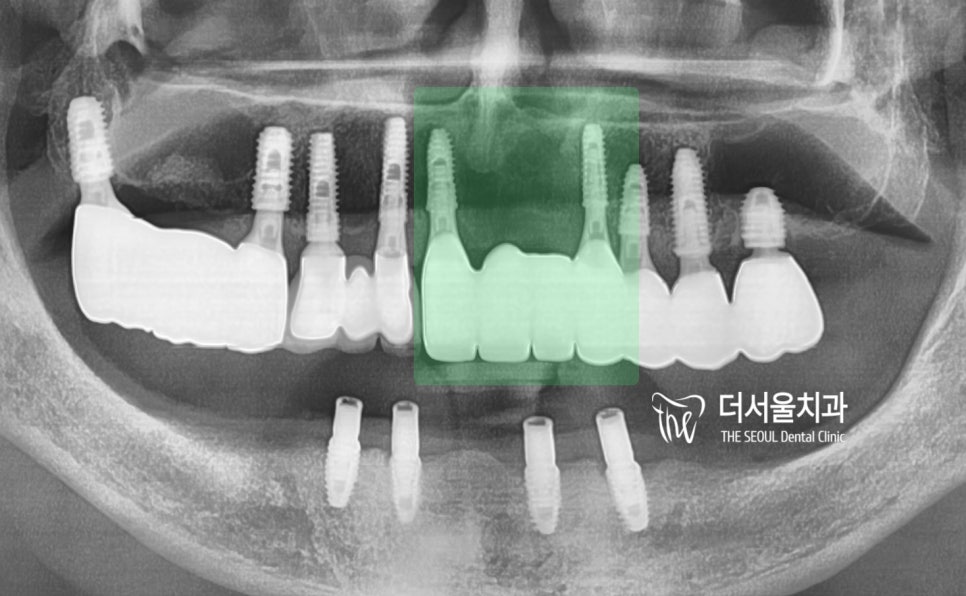

치근단 엑스레이를 보면

이 분께서 왜 저를 찾아오셨는지 알 수 있습니다.

이 2가지의 원인 때문에 오시게 된 거고,

이미 구강 내 상당한 통증을 느끼고 계셨습니다.

그리고, 이미 하악에는

overdenture 라는 임플란트 에

틀니를 연결해서 쓰는 보철을 끼고 계셨네요.

* 초록색 : 임플란트 수술을 해야 될 곳

* 핑크색 : 틀니를 끼고 있는 곳